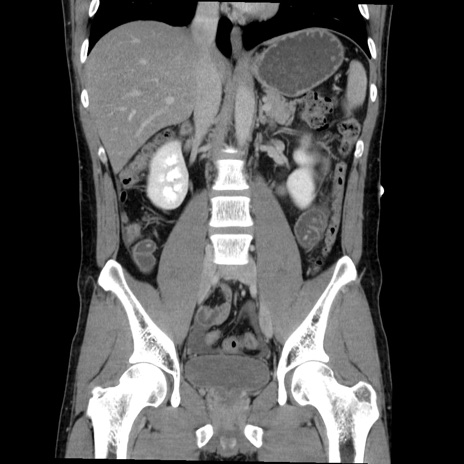

症例36(冠状断像)

【症例】20歳代 男性

【主訴】心窩部痛

【現病歴】今朝より上腹部痛あり。一旦軽快していたが再度出現したため救急要請。昨日夕に白身の魚を含む刺身を食べた。

【身体所見】BP 136/89mmHg、HR 74/min、BT 37.0℃、腹部:膨満、軟、心窩部に圧痛あり。反跳痛なし、筋性防御なし、腸雑音やや亢進あり。

【データ】WBC 17700、CRP 0.48